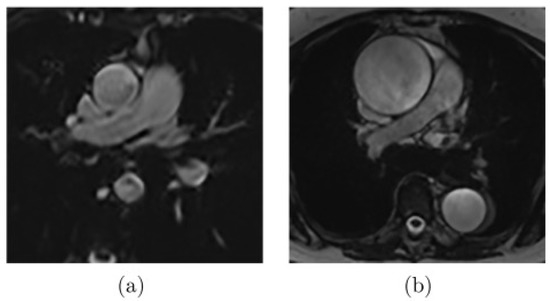

A cardiac MRI was performed before the cardiac surgery to determine, in particular, the aortic compliance. Images were collected using a 3T MRI (Skyra, Siemens Healthineers, Erlangen, Germany), with a specific acquisition in addition to the standard protocol. This acquisition is a FLASH-type sequence undertaken during a short breath-hold in the transverse plane at the level of the pulmonary artery bifurcation, as shown in Figure 1. Since it is less sensitive to noise caused by rapid or turbulent flow at 3T, this sequence was chosen over a steady state free precession (SSFP)–type sequence. This plane allows us to examine both the ascending and descending thoracic aortas. Images at all phases of the cardiac cycle were obtained with a temporal resolution of 20 ms to 34 ms thanks to a retrospective ECG-gating, with the following sequence settings: echo time of 3.42 ms, repetition time of 7.21 ms, flip angle of 12°, spatial resolution between 1.09 × 1.09 mm/pixel, and 1.25 × 1.25 mm/pixel (corresponding to a field of view ranging from 350 mm to 400 mm), and slice thickness of 5 mm. A generalized auto-calibrating partially parallel acquisitions (GRAPPA) was performed, with an acceleration factor of two. A pre-scan normalized filter and distortion correction were also applied.

Figure 1.

Axial MRI at the level of the pulmonary trunk.